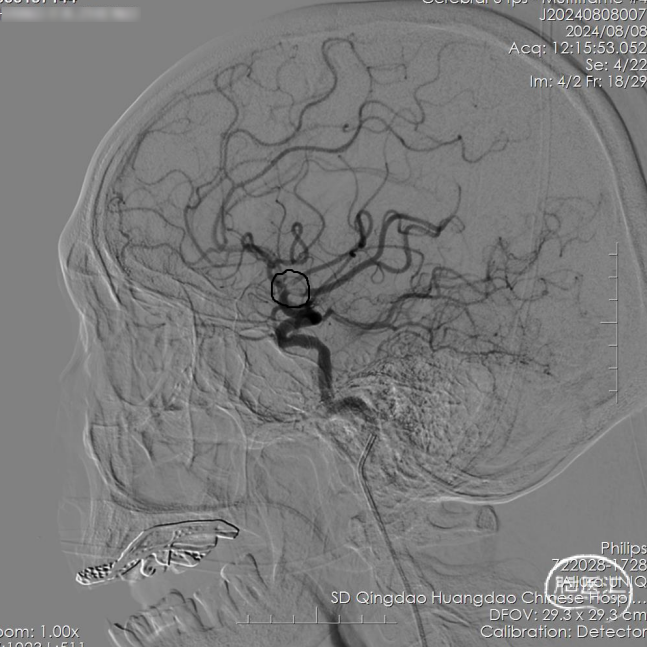

造影示:左侧颈总动脉显示左侧颈内动脉、大脑前动脉及其分支显影好,左侧大脑中动脉上干前向血流缓慢,提示闭塞。

结合头颅CT检查及临床症状(神志不清,失语,凝视,右侧肢体瘫痪),考虑左侧大脑中动脉上干栓塞为责任病变,根据患者病情,经研判后准备给予镇静下脑动脉血栓取出术,沿股动脉鞘送入6F长鞘(内衬5F多功能导管,预接Y阀及压力滴注)至左侧颈总动脉远端,撤出泥鳅导丝及多功能导管,沿长鞘送入5F 125cm Tethys AS®血栓抽吸导管(内衬0.014inch 215cm DCwire®微导丝及0.021inch 150cm 微导管)至左侧大脑中动脉远端,Tethys AS®血栓抽吸导管精准到位,撤出DCwire®微导丝、微导管。

5F 125cm Tethys AS®血栓抽吸导管外接50ml注射器负压抽吸,关闭所有滴注,ADAPT技术,抽吸出黑色血栓成分,冒烟见血管再通,造影显示左侧颈内动脉、大脑中动脉、大脑前动脉及其分支显影好,前向血流TICI分级3级。